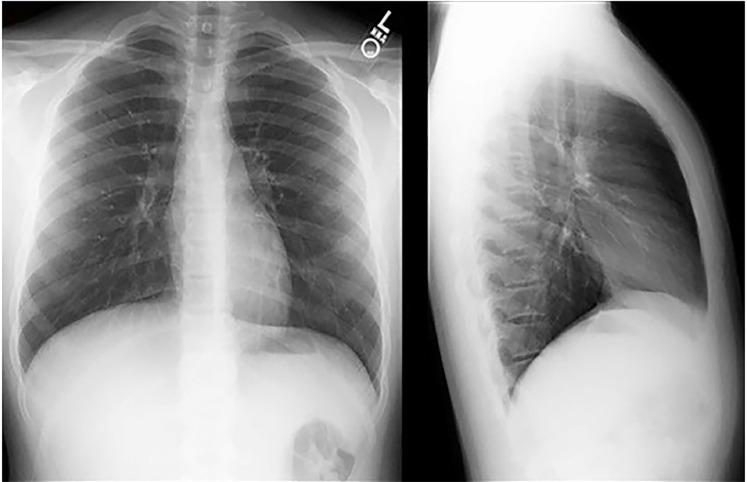

83-year-old Woman with a Fever and Emesis.

Birch Shelly, Dubbs Sarah B, Bontempo Laura J, Dezman Zachary D W

University of Maryland Medical Center, Department of Emergency Medicine, Baltimore, Maryland.

University of Maryland School of Medicine, Department of Emergency Medicine, Baltimore, Maryland.

Clin Pract Cases Emerg Med. 2018 Oct 16;2(4):276-282. doi: 10.5811/cpcem.2018.10.40507. eCollection 2018 Nov.